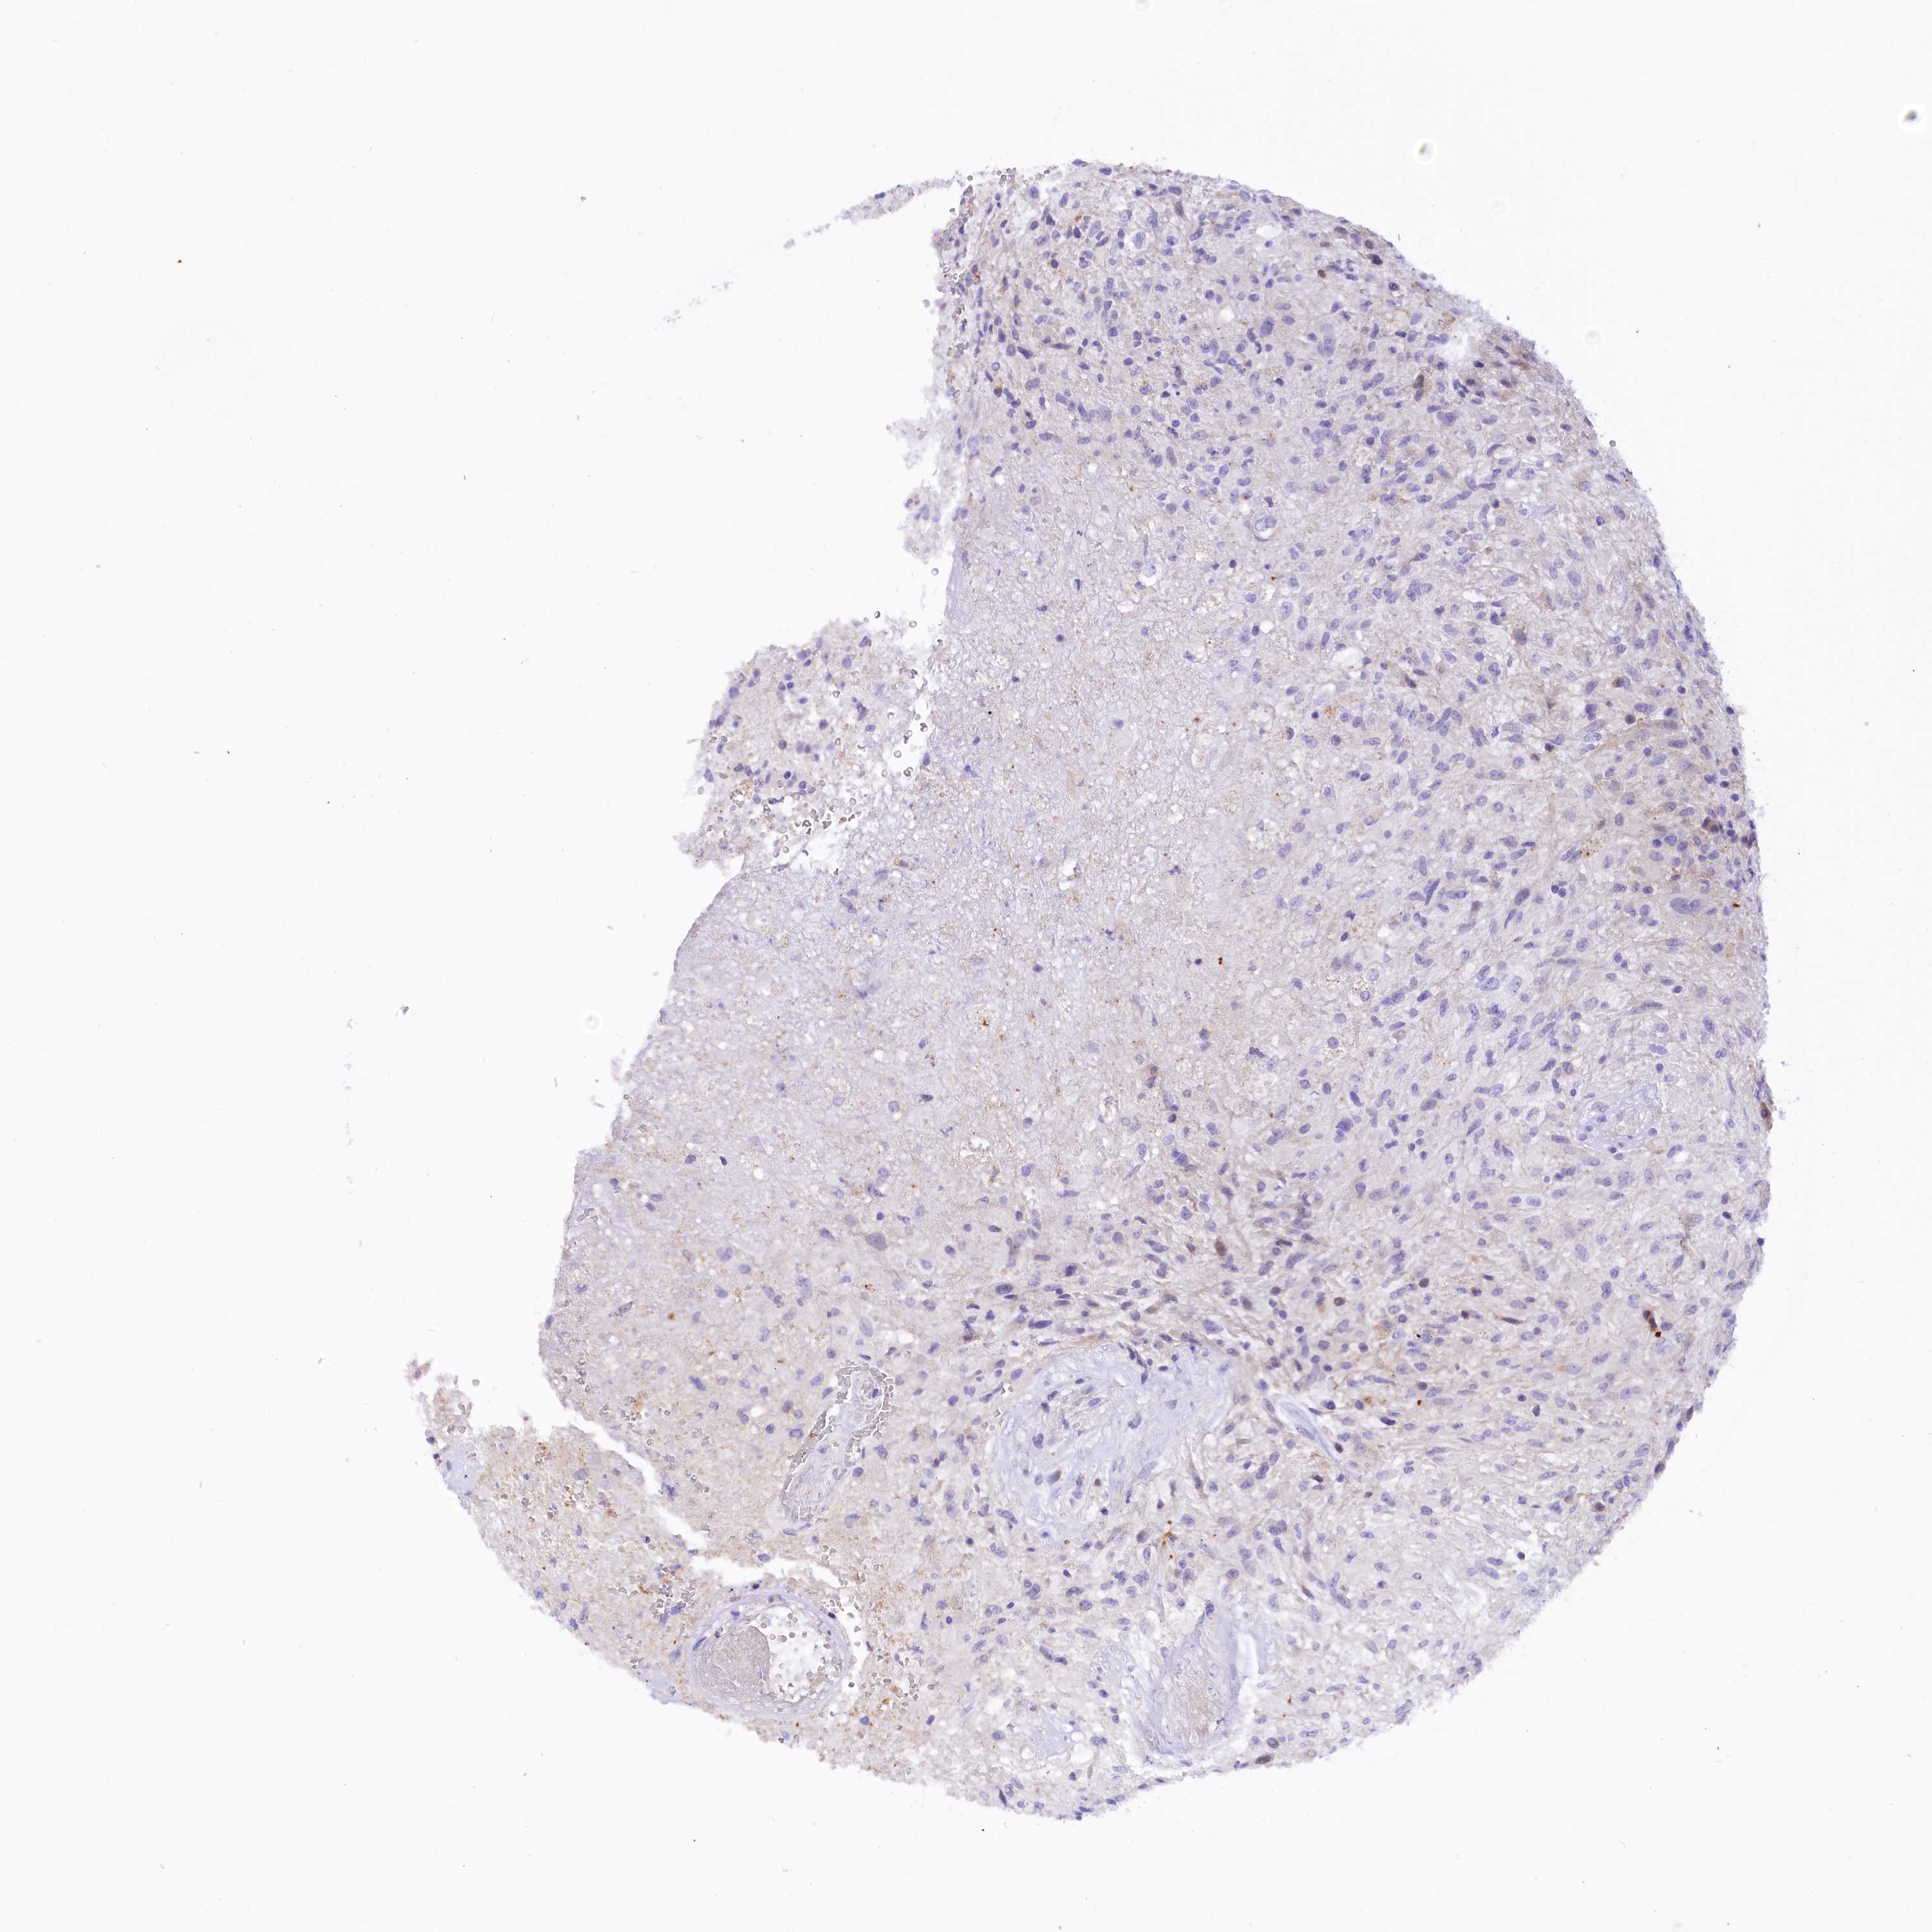

GLIOMA - Protein expressioni

A mouse-over function shows sample information and annotation data. Click on an image to view it in a full screen mode. Samples can be filtered based on level of antibody staining by selecting one or several of the following categories: high, medium, low and not detected. The assay and annotation is described here.

Antibody stainingi

Antibody staining in the annotated cell types in the current human tissue is reported as not detected, low, medium, or high, based on conventional immunohistochemistry profiling in selected tissues. This score is based on the combination of the staining intensity and fraction of stained cells.

Each image is clickable and will lead to virtual microscopy that enables deeper exploration of all samples and also displays staining intensity scores, fraction scores and subcellular localization as well as patient and tissue information for each sample.

Antibody HPA043138

Staining

High

Medium

Low

Not detected

Intensity

Strong

Moderate

Weak

Negative

Quantity

>75%

75%-25%

<25%

None

Location

Nuclear

Cytoplasmic/membranous

Cytoplasmic/membranous,nuclear

Glioma, malignant, High grade

Glioma, malignant, Low grade